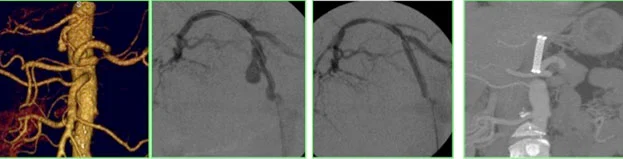

Un aneurisma è la dilatazione patologica di una arteria viscerale con un diametro almeno 1.5 volte superiore a quello normale, che interessa tutti i suoi strati. Questo fenomeno può essere pericoloso, a causa del rischio di rottura.

Le arterie splenica e epatica sono le più comunemente interessate da aneurismi viscerali. In particolare, l’arteria splenica è coinvolta nel 60-70% dei casi, mentre l’arteria epatica rappresenta circa il 20% degli aneurismi viscerali.